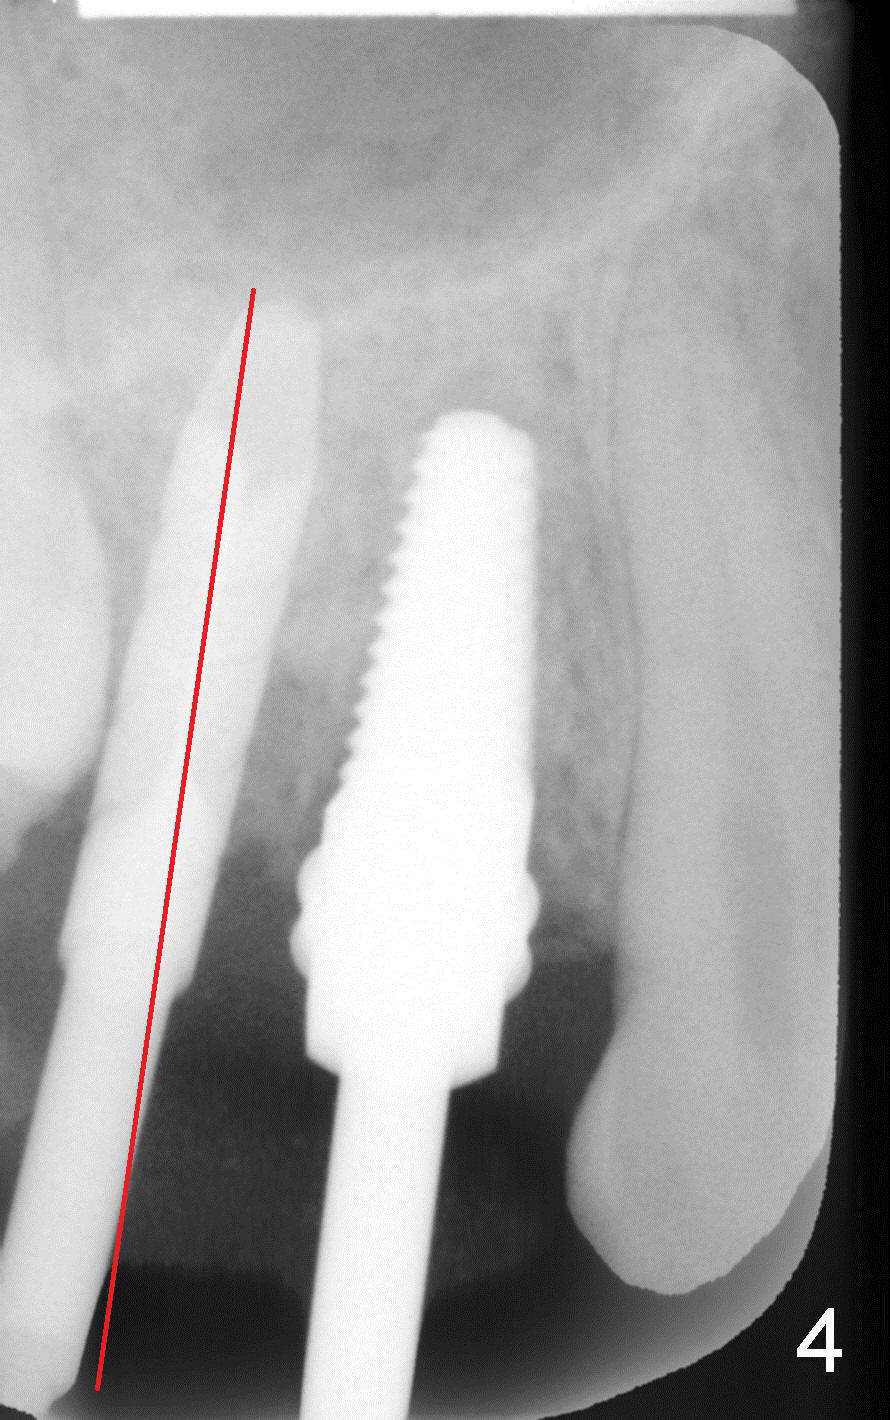

8. 4.5x17 tap, implants, torque wrench (4.5x11 and 4.5x14 mm tapered implants were placed at the sites of #4 and 5, respectively (Fig.6))

9. Fig.2,3 show pilot drill and guiding pin at the sites of #4 and 5, respectively.  Thanks to our joined effort, the axis of the implant at the site of #4 was corrected from Fig.4 to 6

6. Place implants in the middle of the socket, slightly more palatal (two assistants today did good job in this aspect)